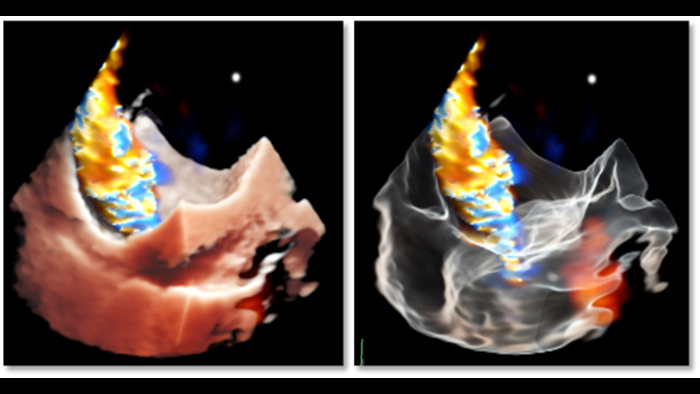

Informações aprofundadas com TrueVue Color e GlassVue

Renderização fotorrealista de Cardiac TrueVue com alinhamento de imagens MultiVue